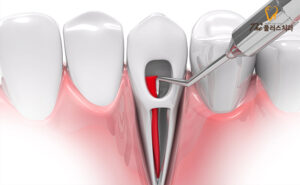

치수에 염증이 있거나 세균에 감염되어서

치아 뿌리 끝에 염증이 일어난 경우에는

근관치료를 시행한 후에도

치아 뿌리 끝 주위에 있는 조직은

치료되지 않는 경우가 많은데요.

이 경우에는 치아 뿌리 끝에 있는

치조골 주위의 염증 조직을

치아 뿌리 끝부분과 함께 잘라내는데

이것을 치근단 수술 또는

치근단 절제술이라고 합니다.